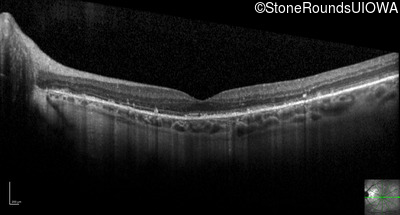

Optical Coherence Tomography - Right - 20/20 -1

Exemplar / OCT Stack

OCT Stack